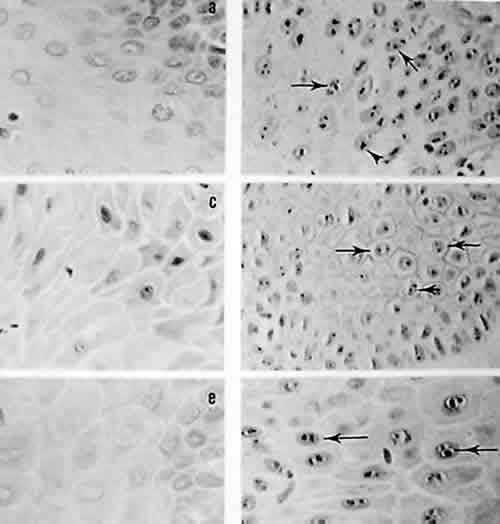

Fig. 1. Fotomicrografía correspondiente a: a) Verruga vulgar, c) Queratosis friccional, e) Displasia epitelial con tinción de H y E, en los incisos b), d) y f) teñidos con plata coloidal se aprecian los puntos nucleolares en las respectivas lesiones a 100x.